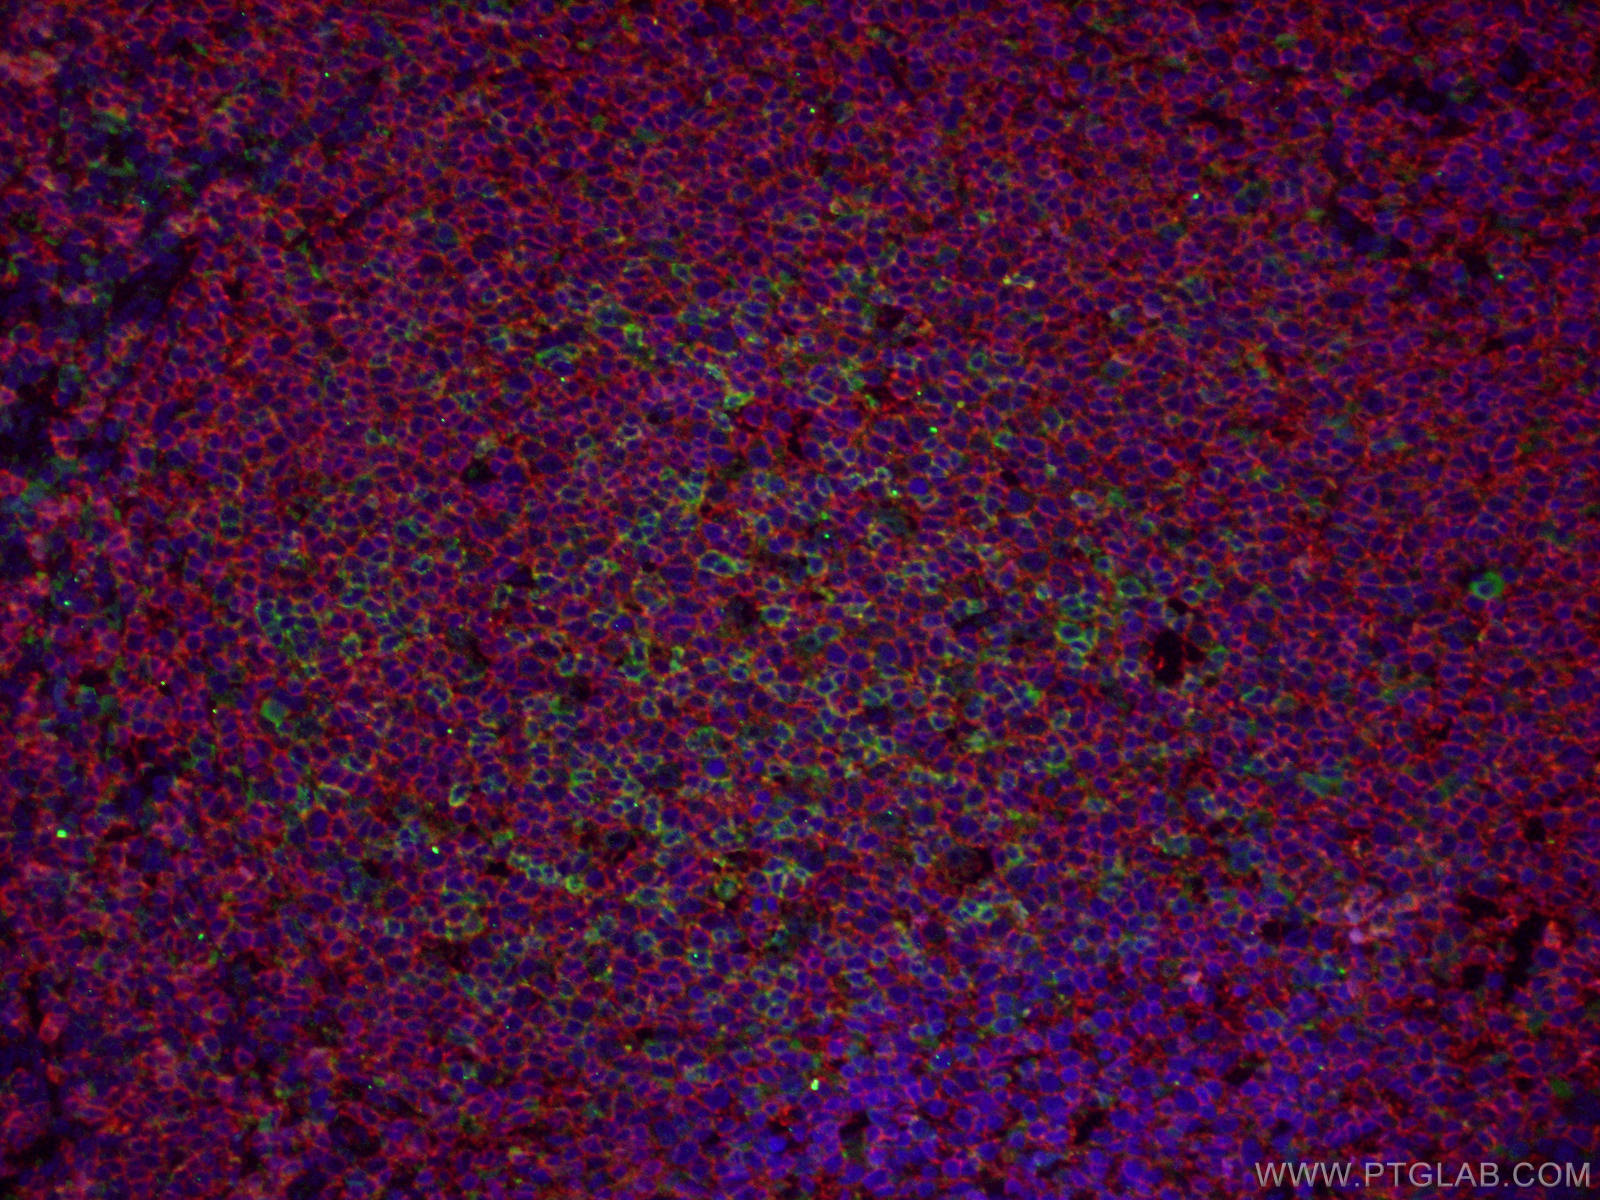

| Positive IF-P detected in | human tonsillitis tissue, Raji cells |

24828-1-AP targets CD20 in WB, IHC, IF/ICC, IF-P, IP, ELISA applications and shows reactivity with human samples.

CD20 is a 33-37 kDa transmembrane phosphoprotein. CD20 is a B-lymphocyte surface molecule that is widely expressed during B-cell ontogeny, from early pre-B-cell developmental stages until final differentiation into plasma cells. CD20 functions as calcium-permeable cation channel. It is involved in the regulation of B-cell activation and proliferation. CD20 serves as a useful target for antibody-mediated therapeutic depletion of B-cells.